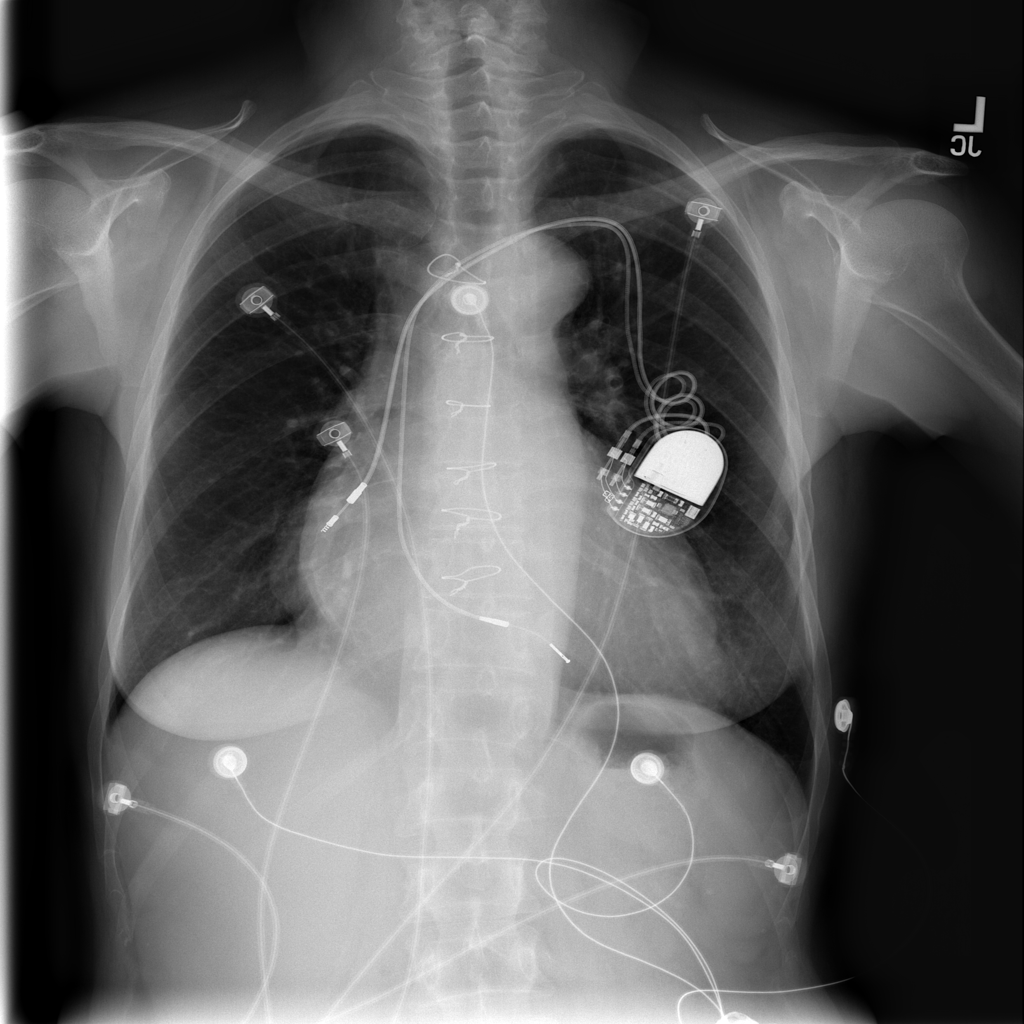

PAT-AE5C · IMG-000Cardiomegaly

PAT-AE5C · IMG-000

PA